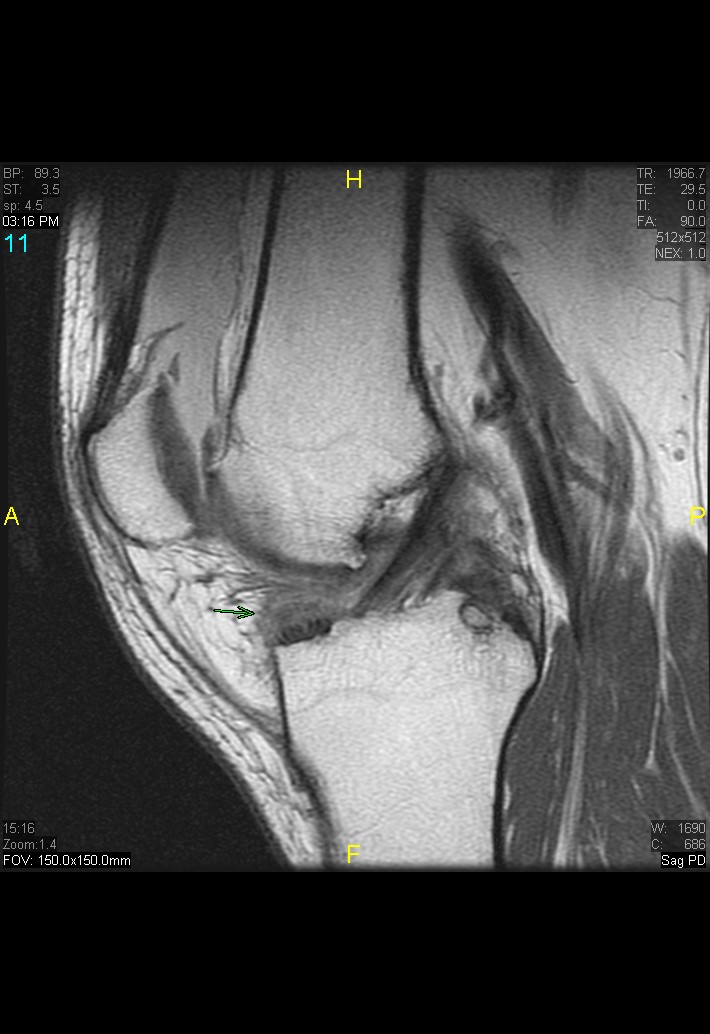

Figure 1 for case gout arthritis ( RID3567 )

Figure 1